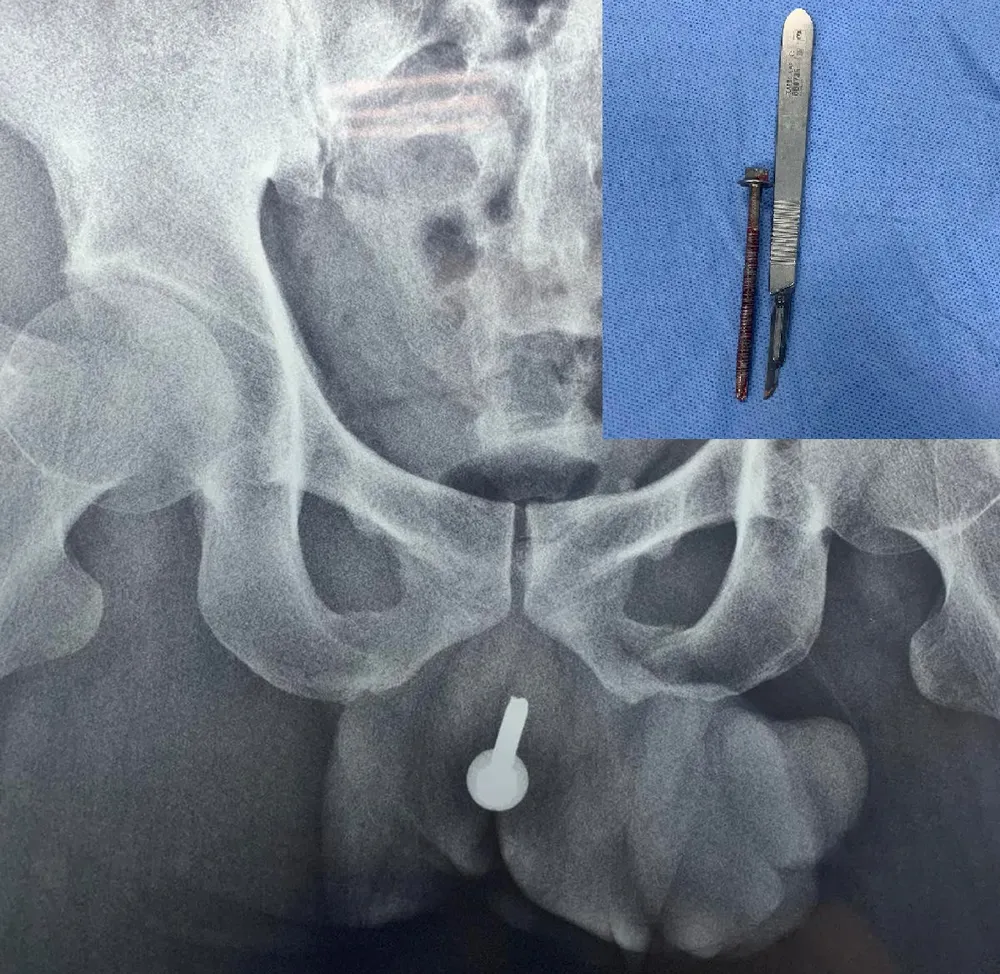

Tại đây, các BS phát hiện dị vật dài khoảng 6 cm nằm dọc theo niệu đạo gây nhiễm trùng, áp xe vùng niệu đạo của bệnh nhân.

Bệnh nhân được mổ cấp cứu chuyển lưu nước tiểu bằng cách mở bàng quang ra da để hạn chế nhiễm khuẩn. Tiếp tục nội soi, các BS phát hiện dị vật là chiếc ốc vít có ren xoắn thường dùng trong xây dựng, niệu đạo viêm nhiều, xung huyết, có dấu hiệu nhiễm trùng.

Chiếc đinh vít dài 6 cm trong đường tiểu của bệnh nhân được lấy ra. Ảnh: BVCC

ThS-BS Đỗ Lệnh Hùng, Trưởng Đơn vị Niệu đạo, cho biết khi tiến hành phẫu thuật, êkíp ghi nhận mô niệu đạo trong tình trạng viêm dính, nhiễm khuẩn. Dị vật dài, gây viêm nặng dọc theo niệu đạo nên quá trình bóc tách niệu đạo gặp nhiều khó khăn.